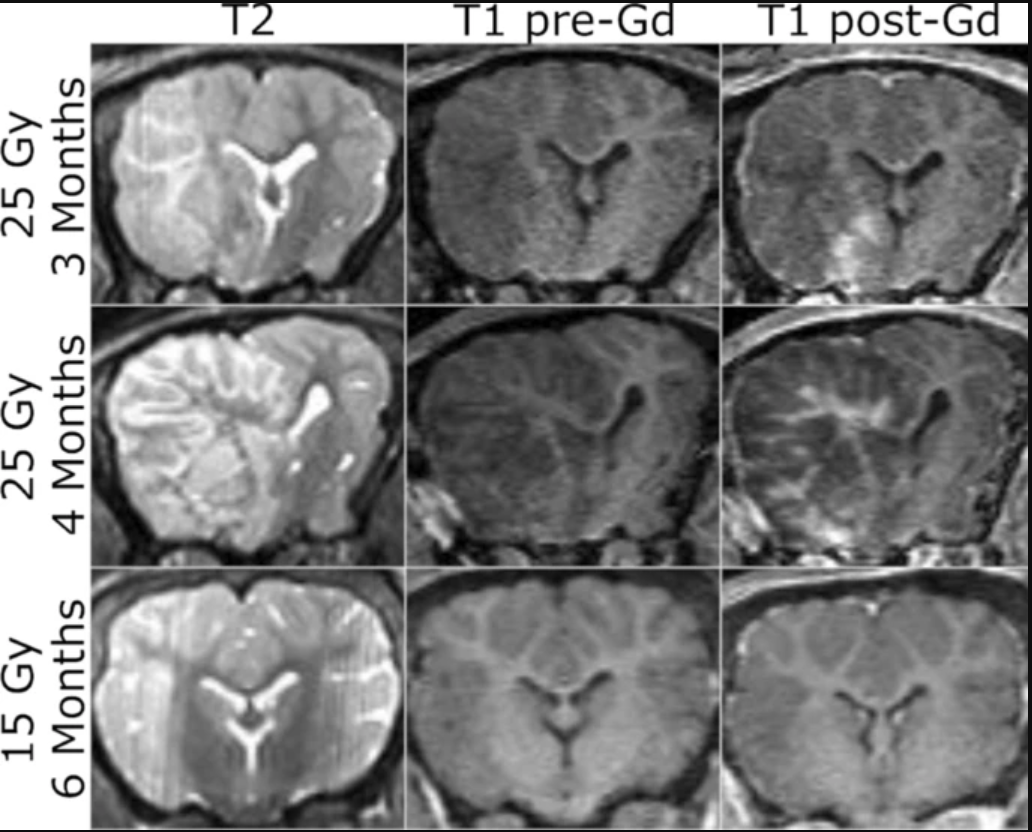

辐照猪脑的MRI表现:最初的计划是在放射后 3 个月和 6 个月时在 3 T 扫描仪上获取大脑的 MR 图像,以检测早期迟发性病理和迟发性RIBI。第一组猪(P1 和 P2)早在放射后 2 个月就出现了明显的神经功能缺陷(左头倾斜和左转)。一头猪(P2)在放射后3个月因不能站立而被安乐死,我们认为这是由于在MRI上观察到脑干损伤所致。另一头猪(P1)在4个月时被安乐死,因为神经功能缺损明显恶化,猪的平衡明显受损。第二只猪的解剖MR图像显示,放射后3个月,T2加权成像有弥漫性增强,与RIBI一致,但发生的时间比预期的要早。放射后 4 个月,观察到的病理变得更加广泛,大量水肿导致中线移位和侧脑室塌陷。第二组猪(P3和P4)在整个6个月的随访期间没有出现神经功能缺损的迹象。

图2、1号小型猪脑左半球放射后的解剖MRI。